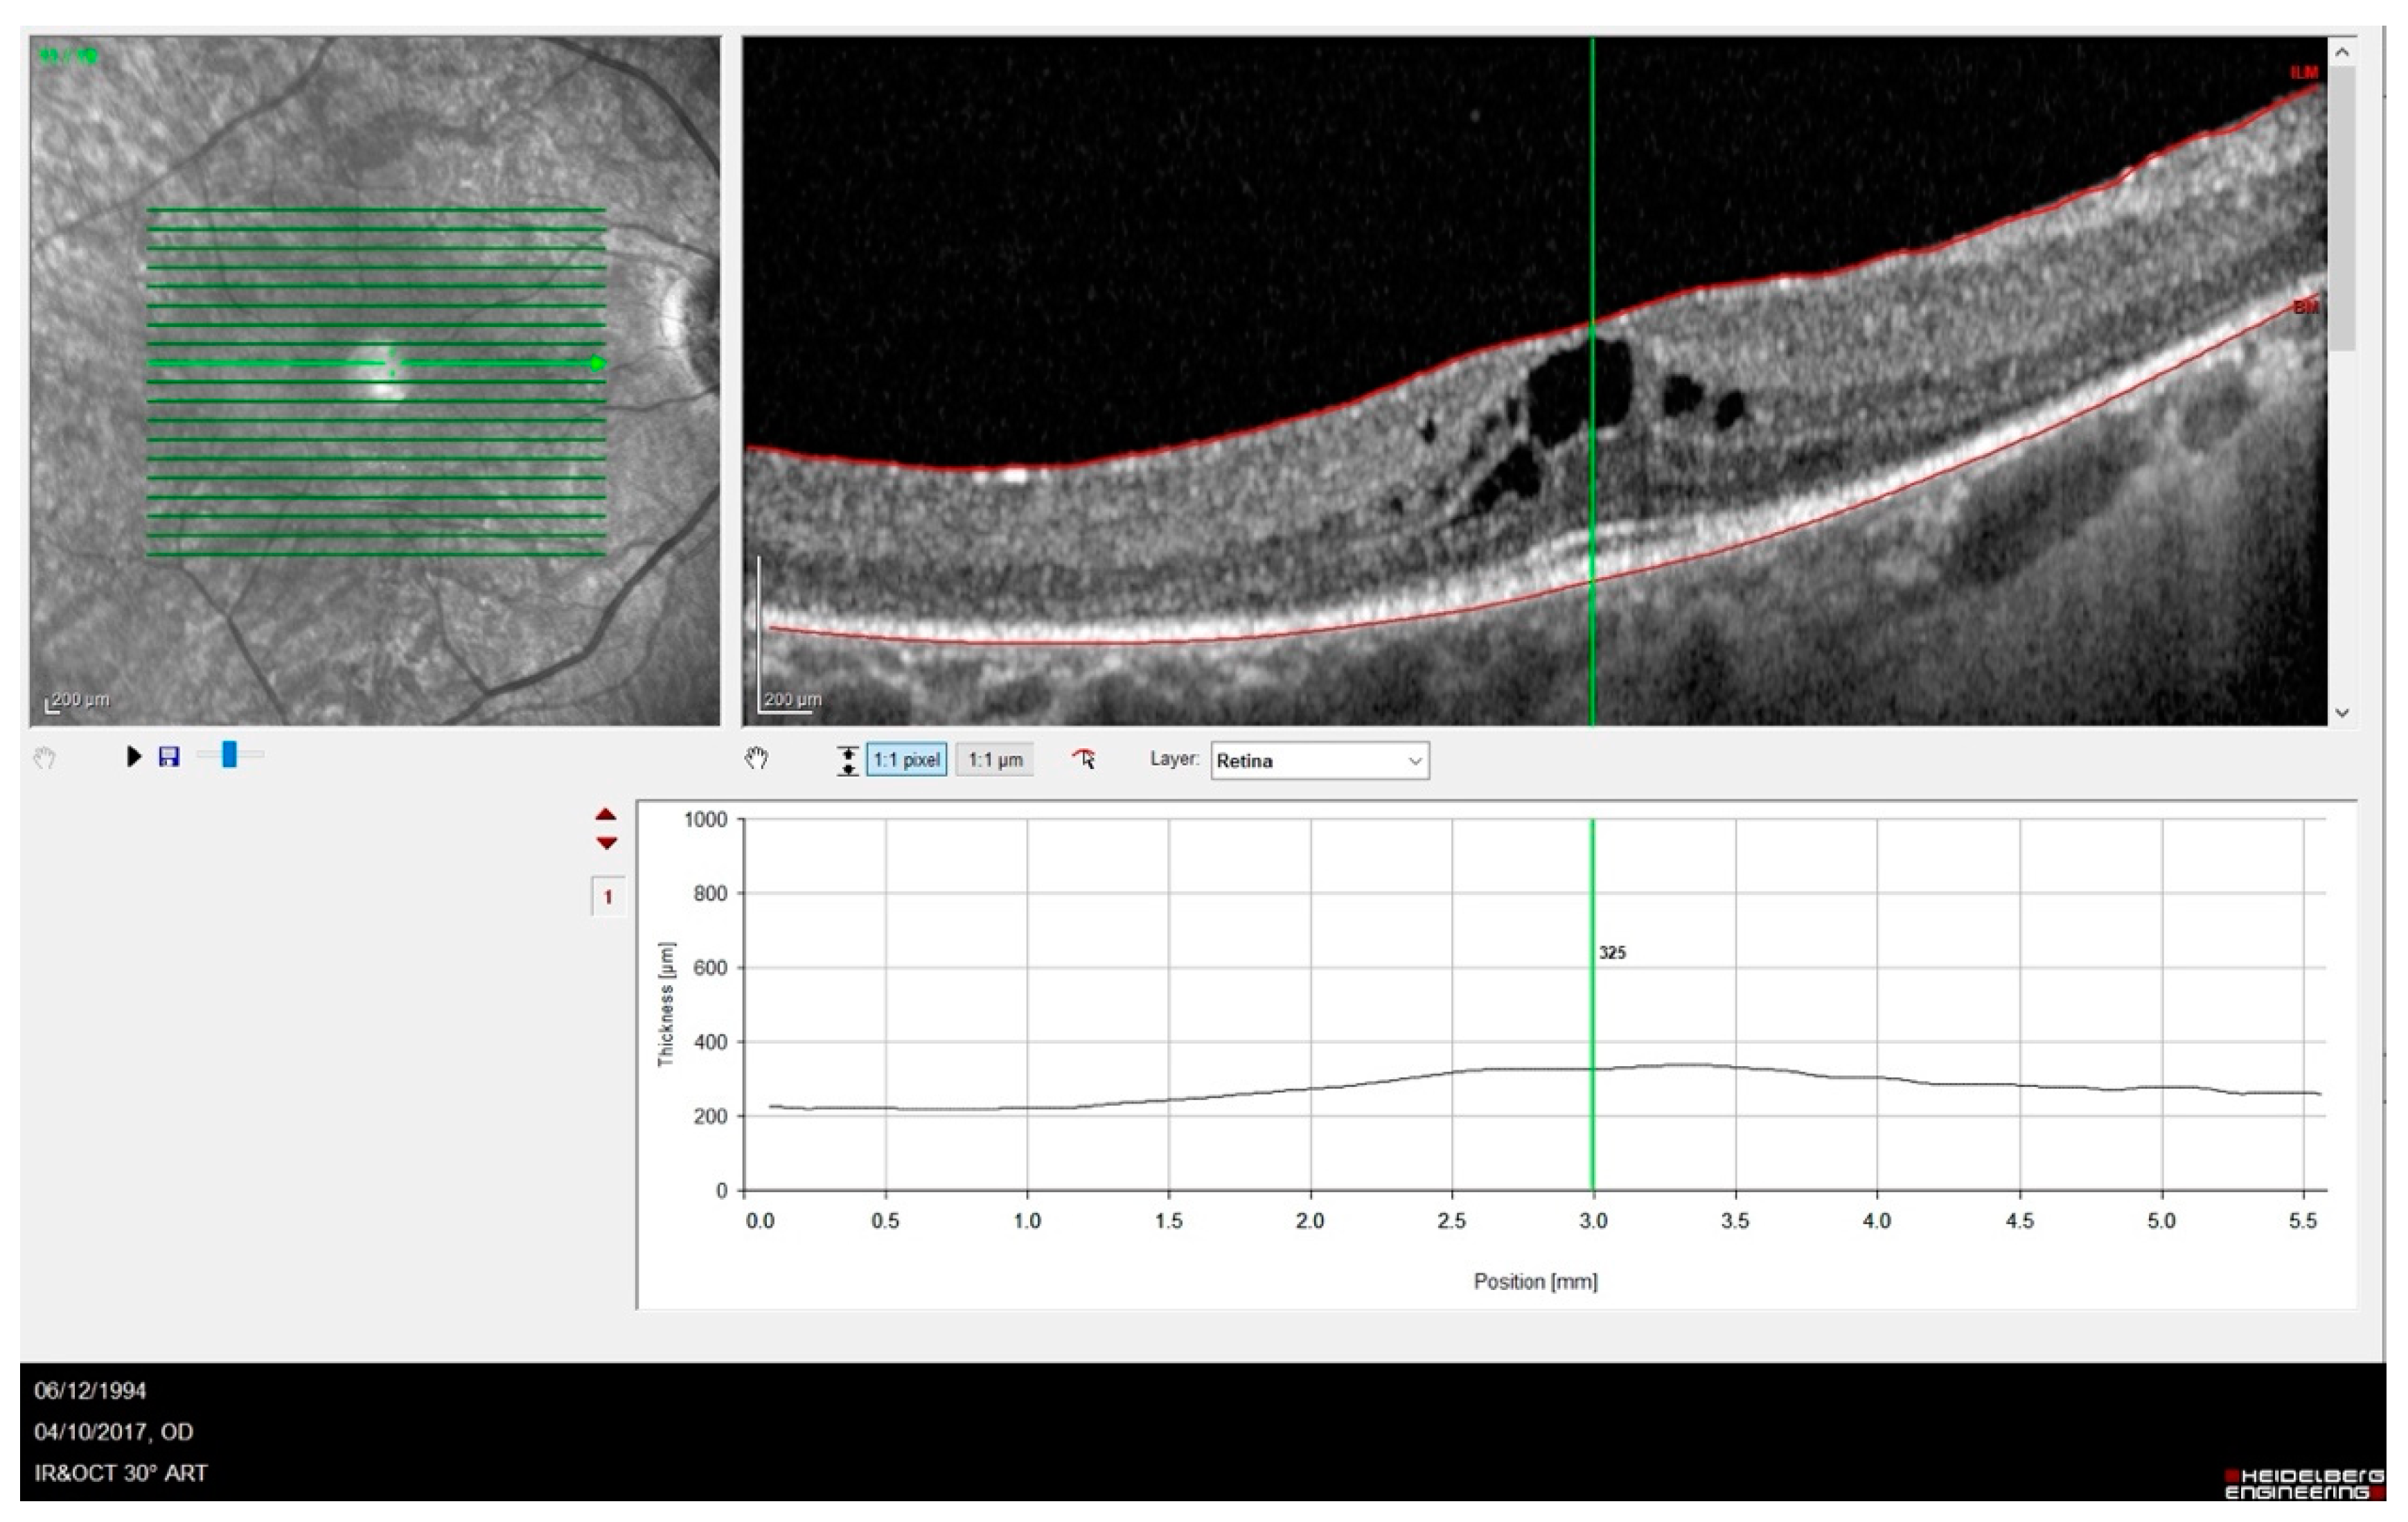

Out of twelve patients (twenty-four eyes), nine eyes were pseudophakic, nine had predominantly posterior cortical cataracts and six had a lens within normal limits. OCT images showed some abnormalities in the outer retina, e.g., disrupted ellipsoid zone (EZ) and thinning of the outer nuclear layer. OCT evaluation of the macular area detected cystoid macular oedema in five eyes, an epiretinal membrane in three eyes and a macular atrophy in three eyes. Cystoid macular edema in one of our patients is shown in Figure 2.

Figure 2. SD-OCT showing a case of RP complicated by cystic macular oedema. It is possible to observe the absence of the foveal depression and IS-OS disruption with outer layer atrophy sparing only of a small subfoveal area.